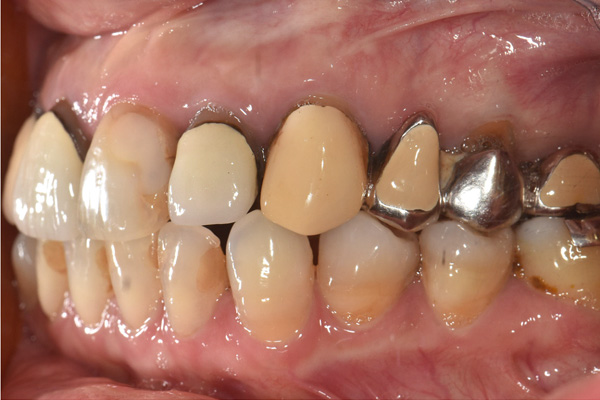

| 年代・性別 | 50代 男性 |

|---|---|

| 主訴 | 右上下の歯が痛い |

| 治療期間 | 約12ヶ月 |

| 費用 | 2,500,000円 |

| 治療内容 | インプラント、骨造成、結合組織移植、セラミック修復 |

| 治療に伴うリスク | インプラント周囲炎 セラミックの破折、脱離 |